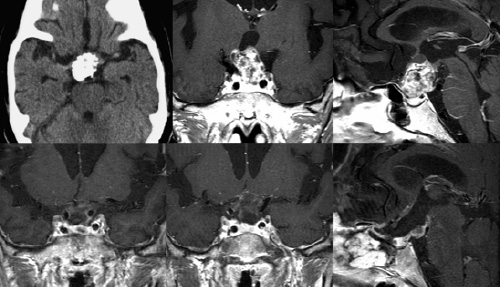

64歳女性 頭蓋咽頭腫

視力視野障害、下垂体機能低下、尿崩症で発症しました。

内視鏡下経鼻頭蓋底手術を行い、下垂体茎部を残して全摘しました。閉鎖には腹部から採取した筋膜によるパッチ縫合を行いました。残存部にはガンマナイフ照射を行い経過観察中です。